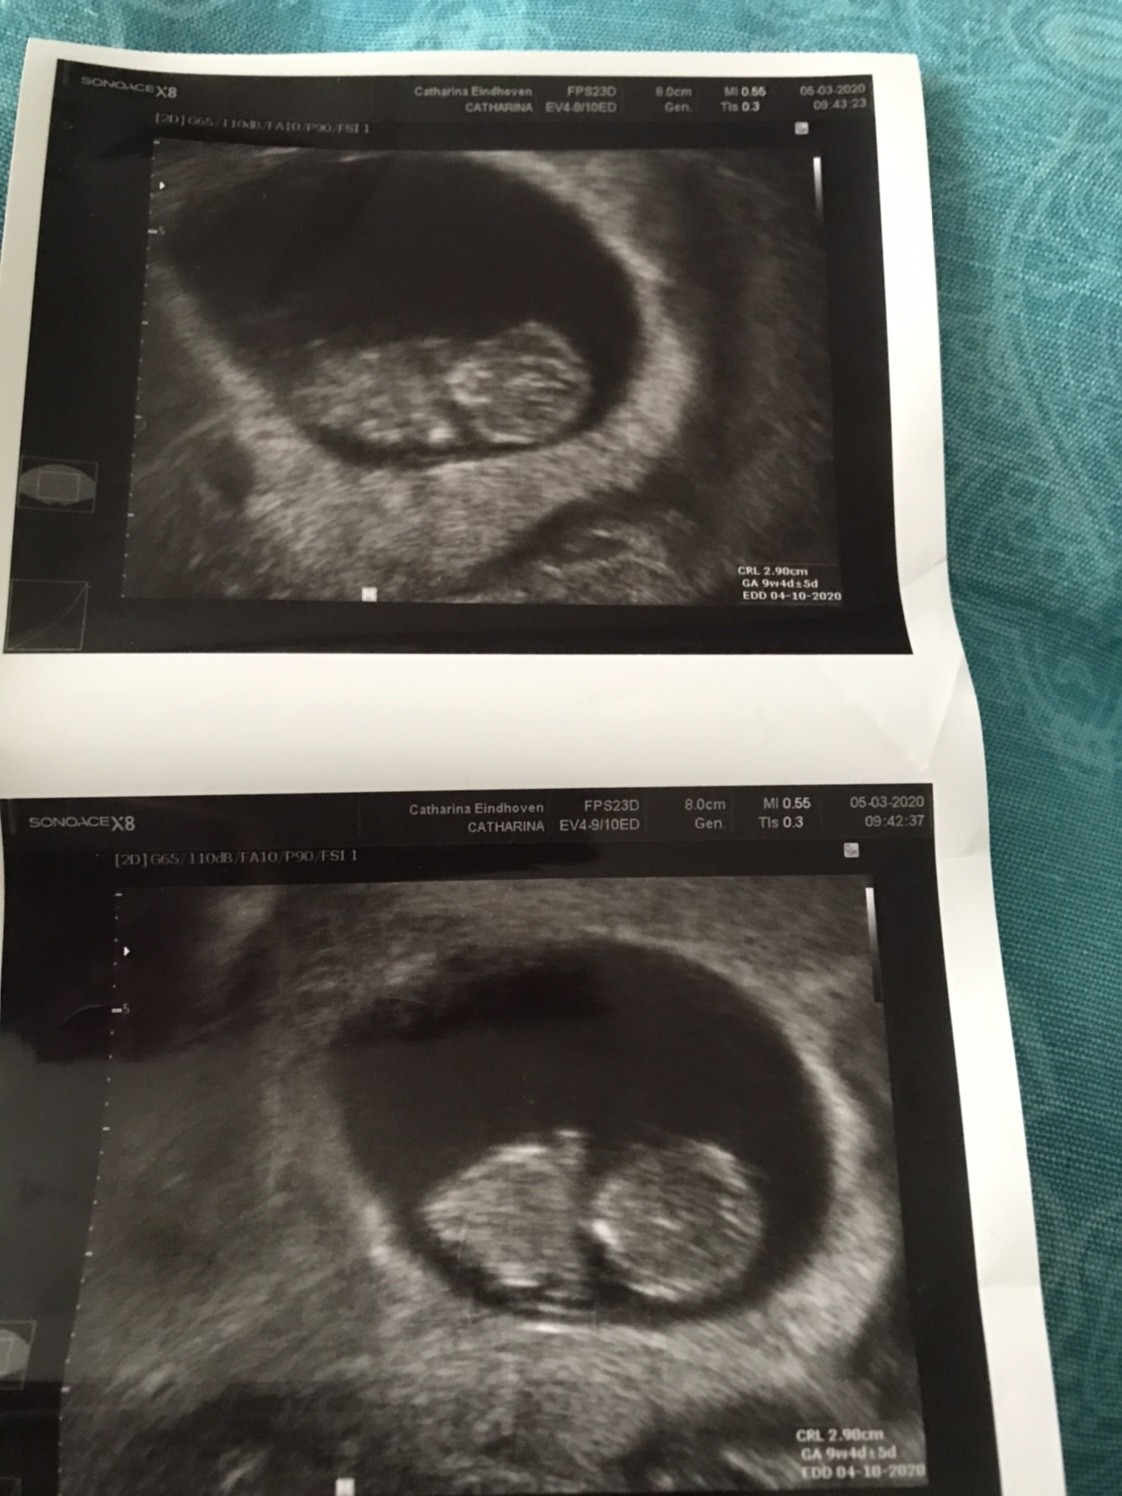

Dziewczyny w końcu dotarłam do domu. A wiec na dzień dzisiejszy wszystko jest dobrze. Maluszek ma nóżki i raczki, kręgosłup i szczękę - i oczywiście serduszko [emoji3059]

Po naciśnięciu ręka brzucha maluszek się ruszał a tak to spał.

Mamy 2,90cm i jest to 9+4 (wg om 9+5)

Termin porodu wpisany w zaświadczenie o ciąży 4.10.2020

A to nasz model/ka